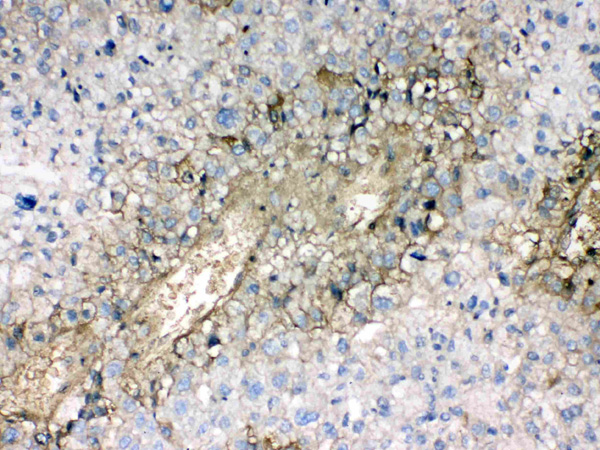

(Figure 3. IHC analysis of Hemoglobin using anti- Hemoglobin antibody (AAA124558).Hemoglobin was detected in paraffin-embedded section of human renal cancer tissues. Heat mediated antigen retrieval was performed in citrate buffer (pH6, epitope retrieval solution) for 20 mins. The tissue section was blocked with 10% goat serum. The tissue section was then incubated with 1ug/ml rabbit anti- Hemoglobin Antibody (AAA124558) overnight at 4 degree C. Biotinylated goat anti-rabbit IgG was used as secondary antibody and incubated for 30 minutes at 37 degree C. The tissue section was developed using Strepavidin-Biotin-Complex (SABC) with DAB as the chromogen.)

(Figure 2. IHC analysis of Hemoglobin using anti- Hemoglobin antibody (AAA124558).Hemoglobin was detected in paraffin-embedded section of human liver cancer tissues. Heat mediated antigen retrieval was performed in citrate buffer (pH6, epitope retrieval solution) for 20 mins. The tissue section was blocked with 10% goat serum. The tissue section was then incubated with 1ug/ml rabbit anti- Hemoglobin Antibody (AAA124558) overnight at 4 degree C. Biotinylated goat anti-rabbit IgG was used as secondary antibody and incubated for 30 minutes at 37 degree C. The tissue section was developed using Strepavidin-Biotin-Complex (SABC) with DAB as the chromogen.)